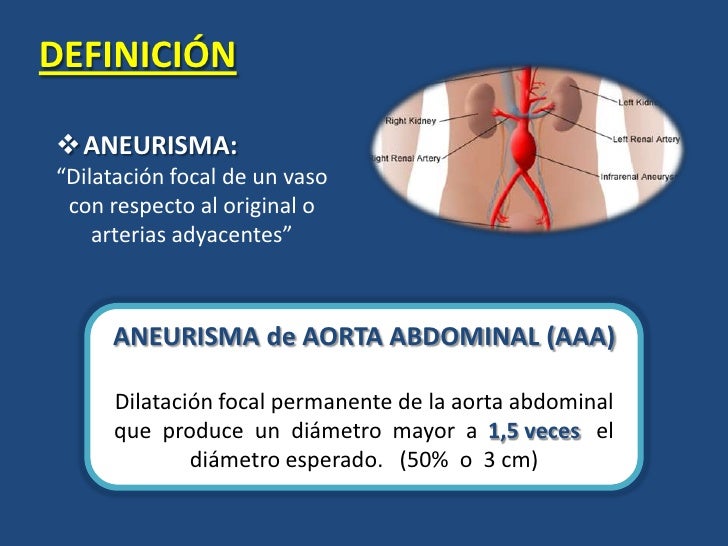

aneurisma de la aorta abdominal La aorta va desde el corazón hasta el. Recibe sangre con gran contenido en oxígeno. Cirugía vascularrupturas de aneurisma de la aorta abdominal: La cirugía de reparación abierta de aneurisma aórtico abdominal (aaa) se realiza para arreglar una parte dilatada de la aorta. Si tienes un aneurisma de la aorta abdominal en expansión, podrías notar lo siguiente: La incidencia de aaai en. En este artículo examen físico pruebas de detección y de diagnóstico ¿quiénes deben someterse a un examen de detección de aneurisma de aorta torácica? Los aneurismas aórticos aneurismas aórticos la aorta, que mide alrededor de 2,5 cm de calibre o diámetro, es la arteria más grande del cuerpo.